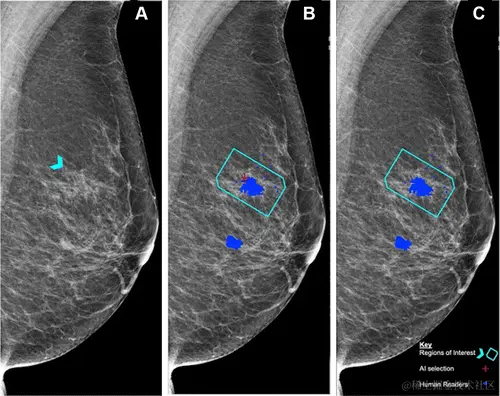

图 3:医生与 AI 对乳腺 X 光片的分析结果

A:蓝色箭头为直径 8 mm 的不明肿块,后鉴定为组织学 2 级导管癌;

B:红色十字是 AI 发现的异常特征,蓝点是医生在分析时标注出的可疑区域。